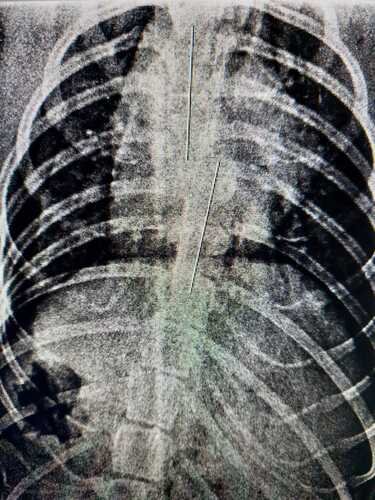

No dia 27, de dezembro, Nina sofreu um acidente de moto ao tentar atravessar a rua da Concórdia, no centro do Recife. Deviso ao impacto, Nina ficou sem o movimento das patas traseiras, já fizemos alguns exames de raio-x, onde constatou-se uma fratura na coluna vertebral, conforme imagem que segue. Nossa luta agora é dar uma vida digna a Nina, precisamos fazer uma Tomografia para saber a extensão da lesão e como vamos poder ajudá-la daqui em diante. Além disso, precisamos comprar uma cadeirinha sob medida para que ela possa se locomover durante o tratamento, com a cadeirinha ela ganha mais dignidade e poderá ter uma vida um pouco melhor.